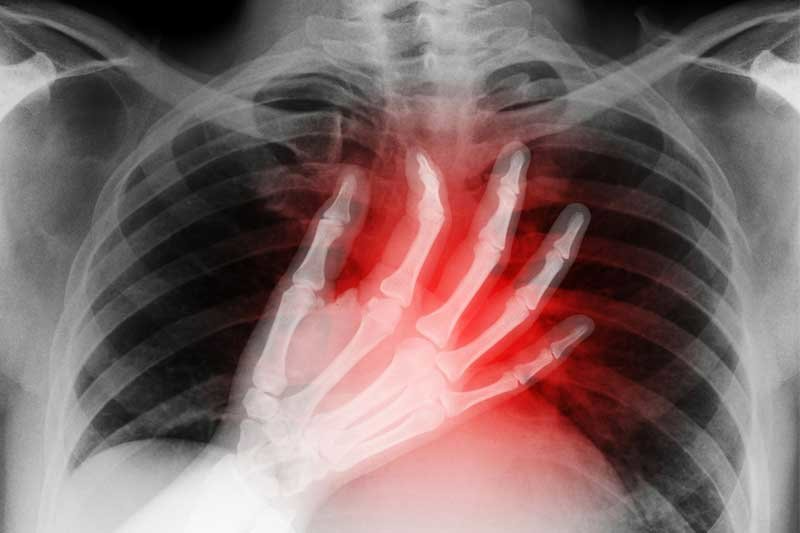

تیر کشیدن رگ قلب احتمالاً شما را به فکر این میاندازد که قلبتان دچار مشکلی شده است. فکر درستی است، ولی این درد میتواند دلایل قلبی و دلایل غیرقلبی داشته باشد و باید بدانید که مشکلاتی کاملاً بیارتباط به قلب هم احتمال دارد باعث شوند شما تیر کشیدن رگ قلب را تجربه کنید.

اطلاع از انواع درد قفسه صدری، راههای درمان و راههای پیشگیری از آن جای مراجعه به متخصص قلب را نمیگیرد ولی حداقل میتوانید تشخیص دهید که درد شما جدی است یا خیر و چه رفتاری را باید در قبال آن پیشه کنید. در ادامه این مطلب ابتدا به سراغ تقسیمبندی علت تیرکشیدن قلب به دودسته قلبی و غیرقلبی رفتهایم.

اولین و مهمترین احتمالی درباره تیر کشیدن رگ قلب که به ذهن شما میرسد و در مرکز درمانی بررسی میشود، احتمال حمله قلبی، آنفارکتوس میوکارد یا سکته قلبی است. حمله قلبی میتواند خطر جانی داشته باشد و رسیدگی به آن را هم نمیتوان به تأخیر انداخت چون ممکن است کار از کار بگذرد.

حمله قلبی زمانی رخ میدهد که جریان خون به قلب مسدود میشود و عضله قلب شروع به مردن در اثر نرسیدن اکسیژن میکند. این اتفاق احتمال دارد در اثر مسدودشدن رگهای خونرسان به یک یا چند عضله قلب با یک لخته خون رخ دهد و فرد سکته کند.

حمله قلبی احتمالاً از دردگرفتن عروق قلب بهصورت لحظهای فراتر میرود و معمولاً باعث درد شدید در قفسه صدری، تنگی نفس، تعریق زیاد، حالت تهوع و استفراغ، سبکی سر و سرگیجه شود. درد حمله قلبی ممکن است به اعضای دیگر بالاتنه تسری یابد.

شما احتمال دارد در شانه، گردن، بازوی چپ و انگشتان دست چپ، فک و سر هم احساس درد کنید. در یک حمله کامل قلبی خونرسانی و در نتیجه اکسیژنرسانی به عضلات قلب کاملاً متوقف میشود.